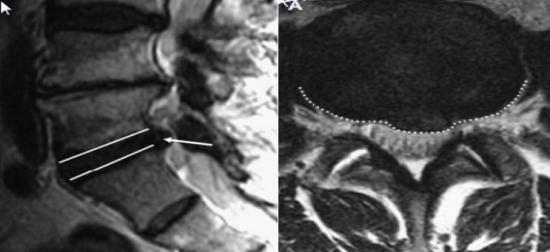

Chụp cộng hưởng từ (MRI).

Chụp cộng hưởng từ (MRI): là xét nghiệm số 1 để đánh giá về cột sống đặc biệt là trong chẩn đoán thoát vị đĩa đệm, cho phép loại trừ các tổn thương bên trong tủy sống.

HÌnh 5: Hình ảnh thoát vị đĩa đệm qua chụp cộng hưởng từ.

(A) tư thế sagittal T2W và (B) tư thế axial T2w